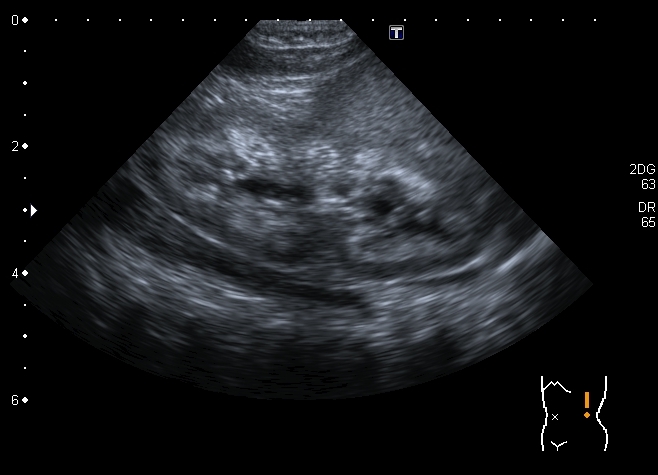

Ребёнок 1-го месяца, оперирован по поводу ВПС, транспозиции магистральных сосудов. В послеопреационном периоде сепсис. Сейчас пришли для обследования перед направлением на МРЭК

Почка Андерсона-Карра. По периферии пирамид определяются эхогенные «кольца» из-за накопления там депозитов кальция.

У детей наиболее частой причиной нефрокальциноза является первичный тубулярный ацидоз и первичная гипероксалурия.